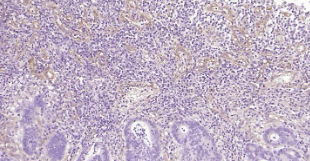

Immunohistochemical analysis of paraffin embedded human colon cancer tissue slide using IHC0238H (Human CD90/Thy1 IHC Kit).